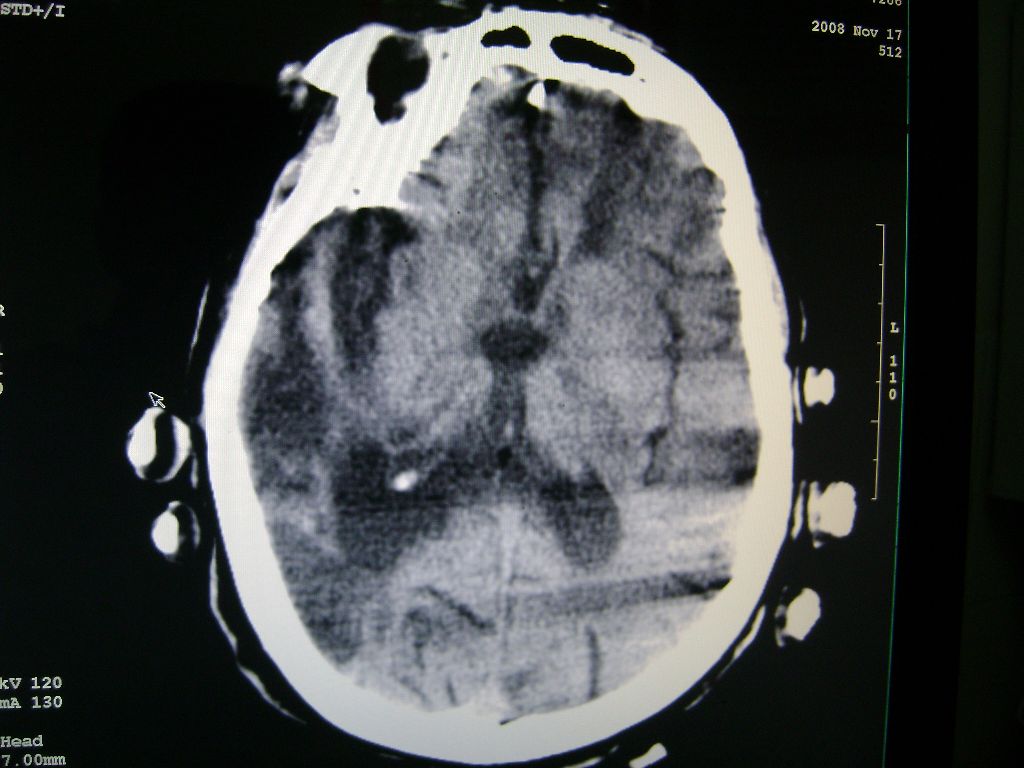

标题: CT16663:F 77 昏迷不醒,各位老师看咯! [打印本页]

f 77 昏迷不醒

出血性脑梗塞

出血性脑梗塞!

右侧额颞枕顶叶脑软化灶,脑萎缩,大脑中动脉壁钙化。

右脑软化灶,考虑再次梗塞,高密度灶出血?钙化?。。。量ct值,改窗宽,位

右脑软化灶,考虑再次梗塞,右顶叶高密度影不像是出血,密度很高,建议量ct值!

右侧半球陈旧性卒中,不除外伴有新病灶,左额叶梗塞,双侧大脑中动脉钙斑

右侧额颞枕顶叶脑软化灶,脑萎缩,大脑中动脉壁钙化。不支持出血(密度高,边界清且局限)顶枕区似有新发梗塞,建议核磁

1)右侧额颞枕顶叶脑软化灶;其内高密度影,多为钙化灶。2)脑萎缩。3)大脑中动脉钙化。

再次脑梗死,右侧额颞枕顶叶脑软化灶,高密度考虑钙化

右侧陈旧脑梗塞伴脑萎缩。脑内点状钙化。大脑中动脉壁钙化灶。无出血灶。

1)右侧额颞枕顶叶脑软化灶并钙化灶可能。2)脑萎缩。3)大脑中动脉钙化。 -